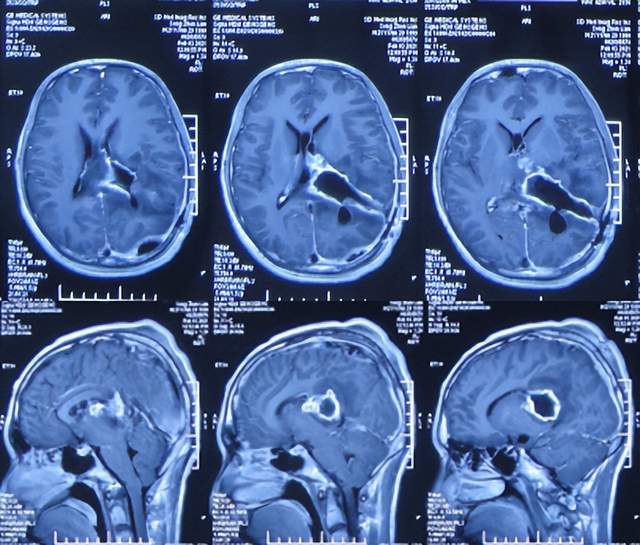

2021年3月12日(左颞角脑室腹壁外引流术后32天,脑脓肿切除术后5天),查头颅CT示仍有少量水肿(图-23)。

图-23:2021年3月12日头颅CT

2021年3月26日(左颞角脑室腹壁外引流术后46天,脑脓肿切除术后19天),夹闭引流管1周左右,颞角没有扩张,因此进行了脑室腹壁外引流管拔除术。

但拔除引流管后11天即2021年4月6日,患者出现头痛,查头颅CT示颞角扩张(图-24)。

图-24:2021年4月6日头颅CT

因此于2021年4月8日,进行了脑室腹腔分流术;术后身体一切正常(图-25)。

图-25:2021年4月9日

于2021年4月18日(治疗近3个月)出院,出院时:身体一切正常。

三、第2次在李小勇脑脊液科治疗过程和结果

出院后5个月即2021年9月中旬,出现偶尔头痛的症状,因此于出院后7个月后即2021年11月10日,第2次来到李小勇脑脊液科;入院时:时有头痛(图-26),身体其他正常;查头颅CT示左侧颞角扩张(图-27)。

图-26:2021年11月10日入院时

图-27:入院时头颅CT

入院后2天即2021年11月12日,给予了颞角分流管调整术;术后第2天查头颅CT示颞角仍扩张(图-28)。

图-28:2021年11月14日头颅CT

入院治疗14天即2021年11月24日,查头颅CT示颞角缩小(图-29),患者头痛基本消失(图-30)。

图-29:2021年11月24日头颅CT

图-30:2021年11月24日

2022年1月4日(李小勇脑脊液科第2次治疗55天)出院。出院时:头痛已消失1月余(图-31),身体一切正常,查头颅CT示未见异常(图-32)。

图-31:2022年1月4日出院时

图-32:出院时头颅CT